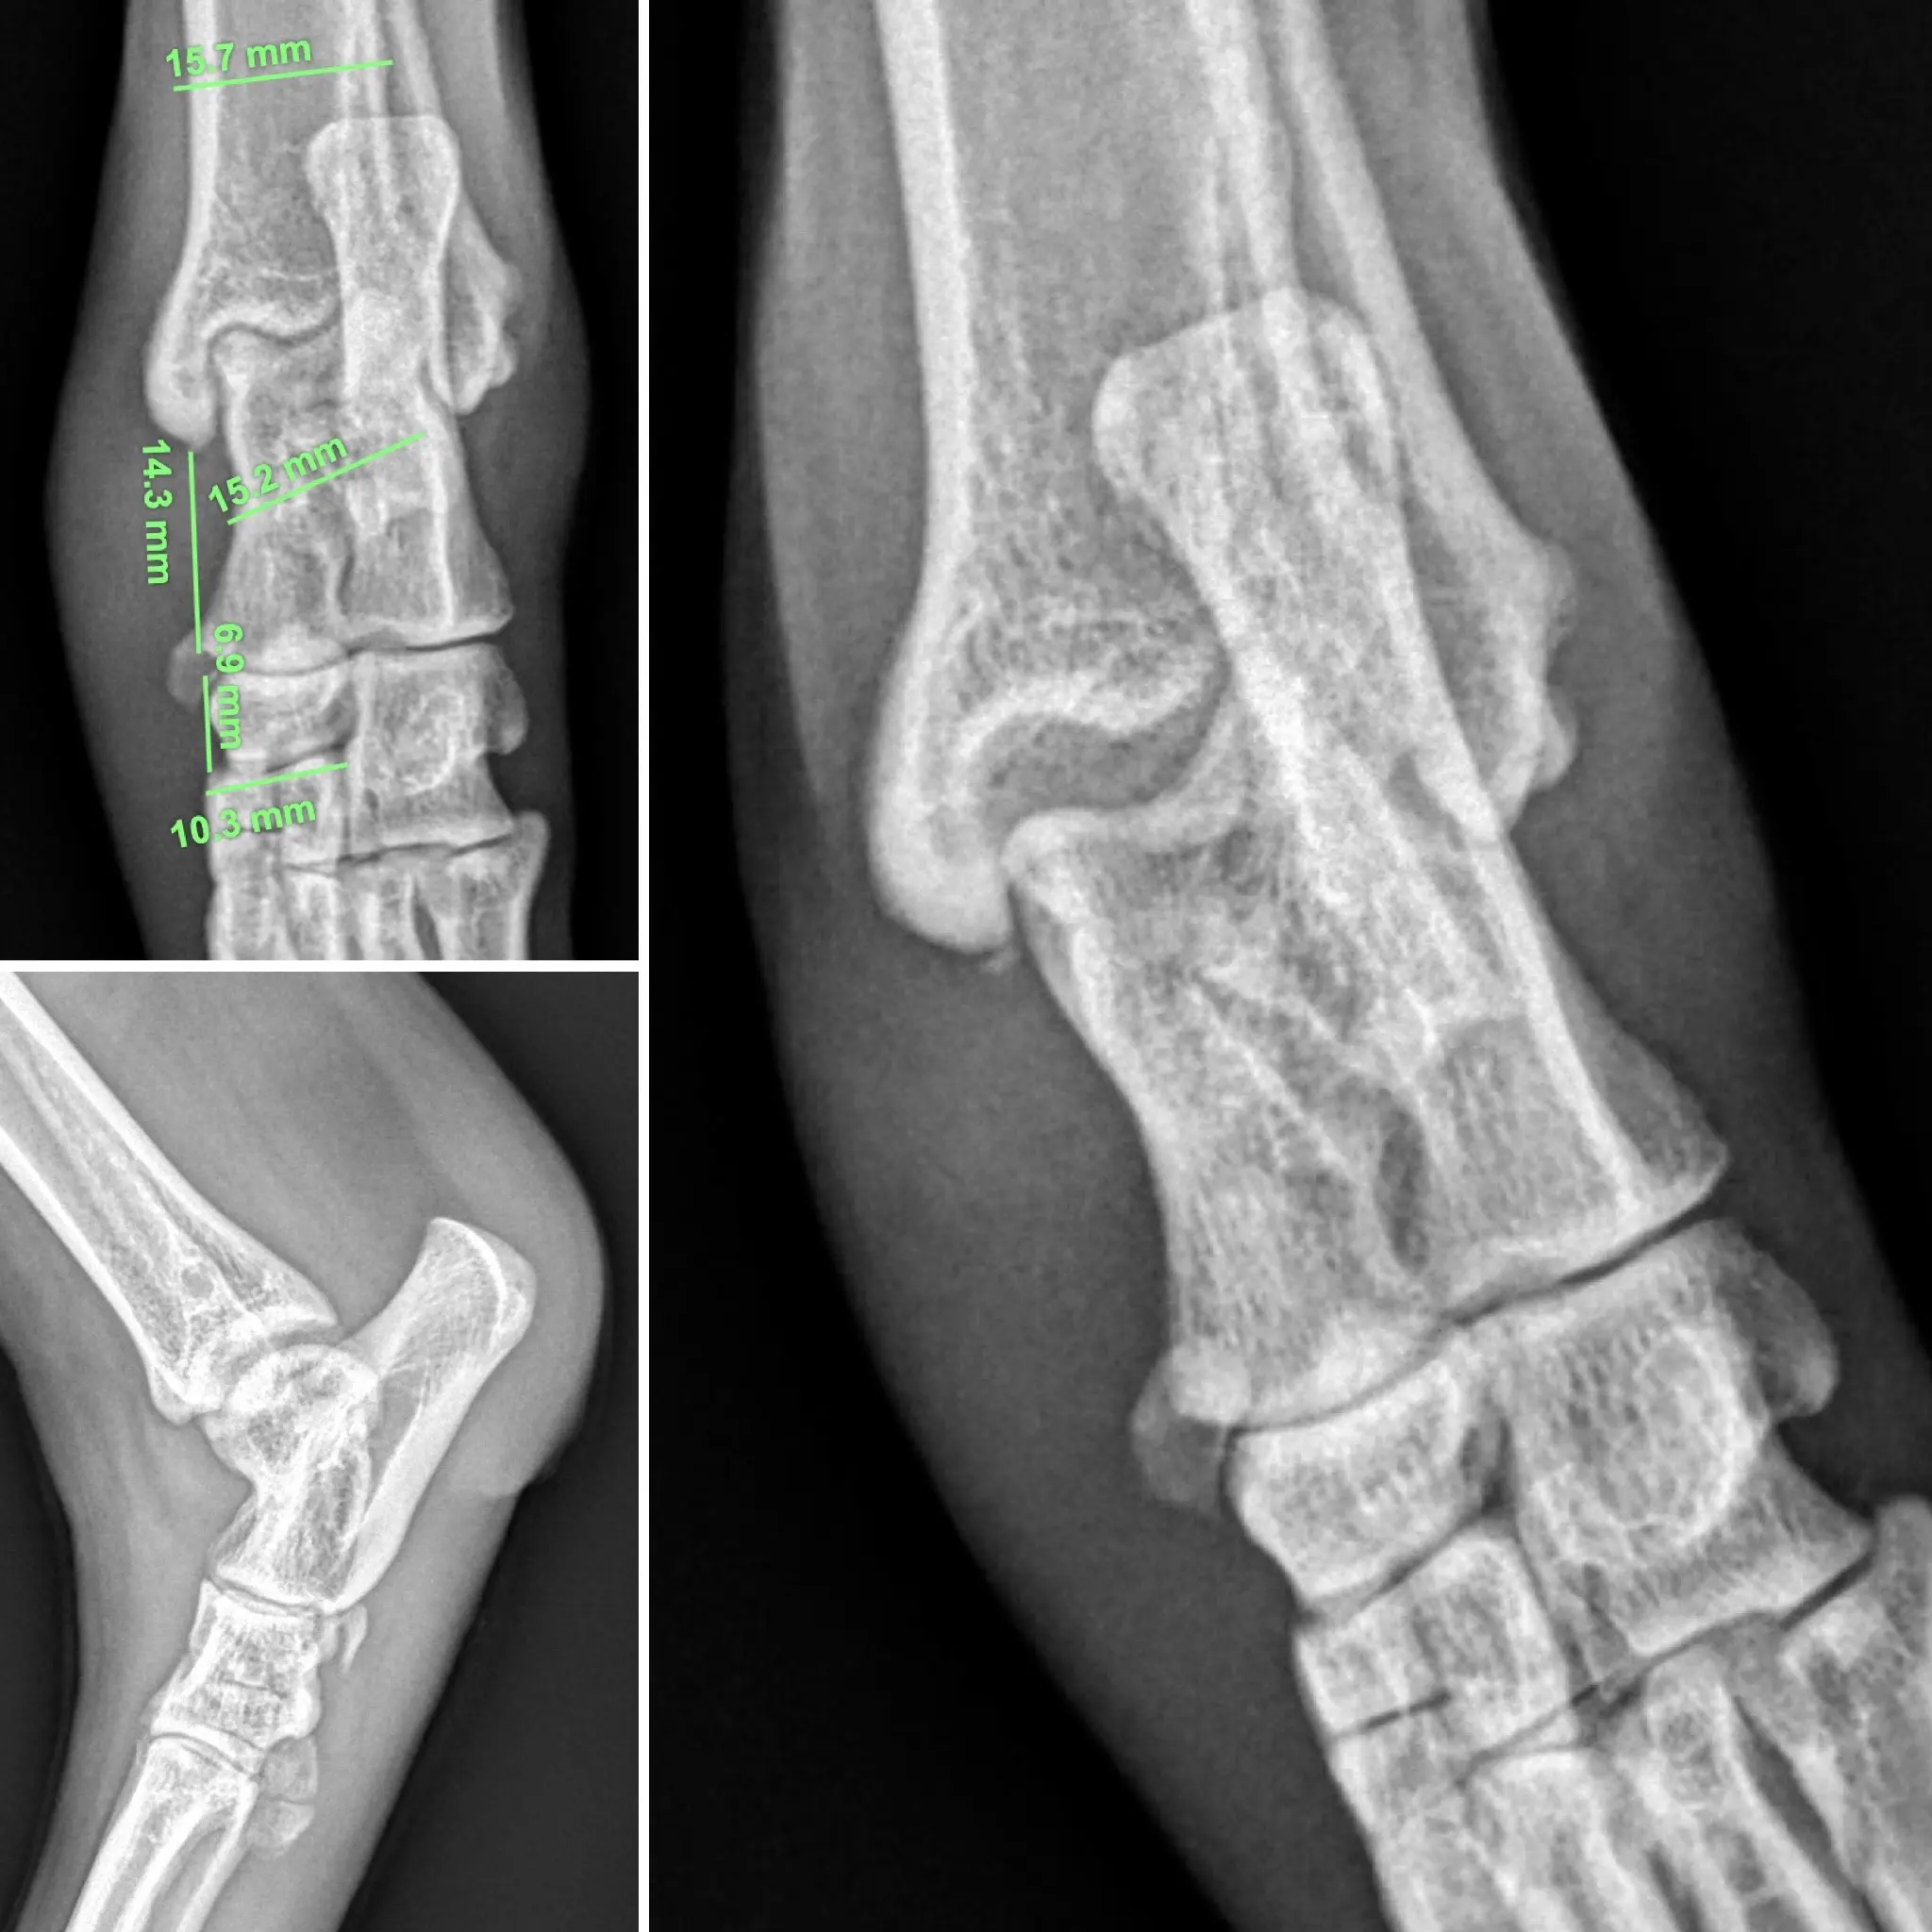

Se realizaron radiografías del tarso afectado tanto en proyecciones fisiológicas como en estrés. En éstas últimas se observó un bostezo articular pronunciado en el aspecto medial, hecho que confirma la incompetencia del ligamento colateral medial del tarso.